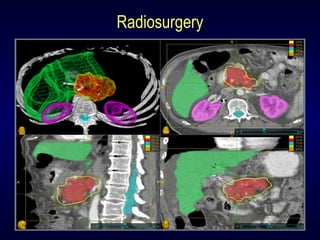

3-D Conformal RT

IMRT

Radiosurgery